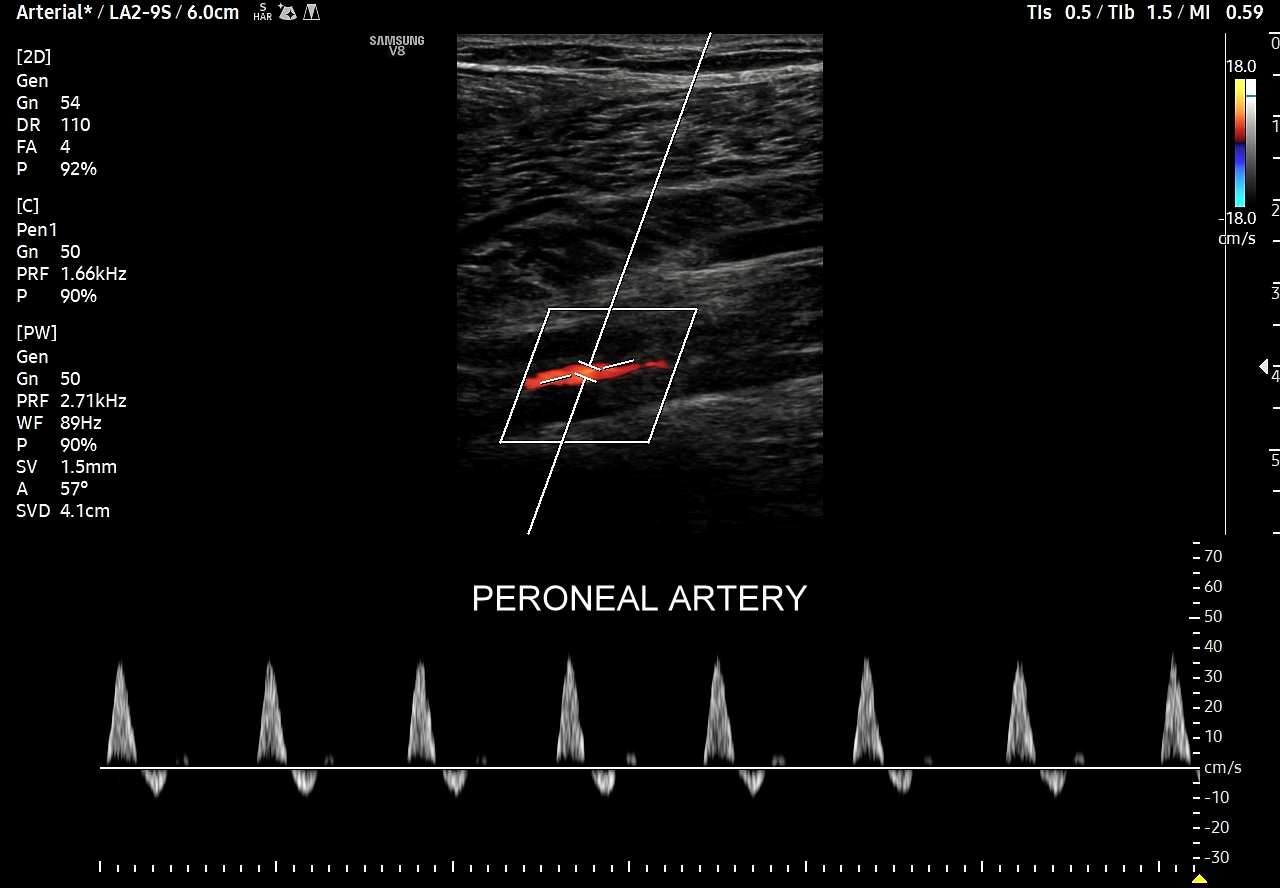

- Z kolei profile o wysokiej pulsacyjności charakteryzują się tym, iż posiadają wąskie i ostre piki skurczowe, a w fazie rozkurczowej odwrócone lub/i nieobecne przepływy. Profile tego typu występują w tętnicach unaczyniających kończyny.

Podsumowując, przepływ krwi w konkretnych tętnicach, w tym jego przyspieszenie i prędkość, wynikają z 1/ charakteru pracy pompy, tj. serca; 2/ stanu naczyń per se, tj. elastyczności i drożności; oraz z 3/ właściwości biologicznych unaczynionego narządu. W związku z powyższym prawidłowy profil przepływu we wszystkich rodzajach tętnic w krążeniu dużym w warunkach fizjologicznych, tj. przy zdrowym sercu, zdrowych naczyniach i zdrowym docelowym narządzie, zawsze cechuje się szybkim narastaniem prędkości przepływu, czyli stromym ramieniem wstępującym; krótkim czasem akceleracji (ang. acceleration time) od początku tegoż ramienia do pierwszego załamania na nim, tj. zasadniczo nie przekracza 70 ms, a zwykle oscyluje wokół 30 ms. Poza tym w przypadku młodych i elastycznych tętnic podążających do kończyn, tj. naczyń z przepływem wysokooporowym, w fazie rozkurczowej przepływu obserwuje się wyższe załamki i często więcej załamków (zamiast jednego nawet do trzech). W krążeniu płucnym czas akceleracji prawidłowo przekracza 100 ms.

W przypadku tętnic podążających do kończyn w warunkach spoczynkowych obserwuje się charakterystyczne wielozałamkowe profile przepływów zawierające od 2 do nawet 4 następujących po sobie przeciwstawnych załamków o zmniejszającej się amplitudzie, przy czym w tętnicach tych zwykle nie obserwuje się ciągłego przepływu w fazie rozkurczowej. Stały lub prawie stały przepływ rozkurczowy, tj. przepływ o pośredniej pulsacyjności, może pojawić się w tętnicach kończyn w trakcie intensywnego wysiłku fizycznego.